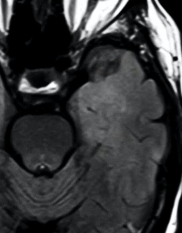

Glioblastome

Decouverte fortuite aux urgences, Confirmé a la patho

Decouverte fortuite aux urgences, Confirmé a la patho